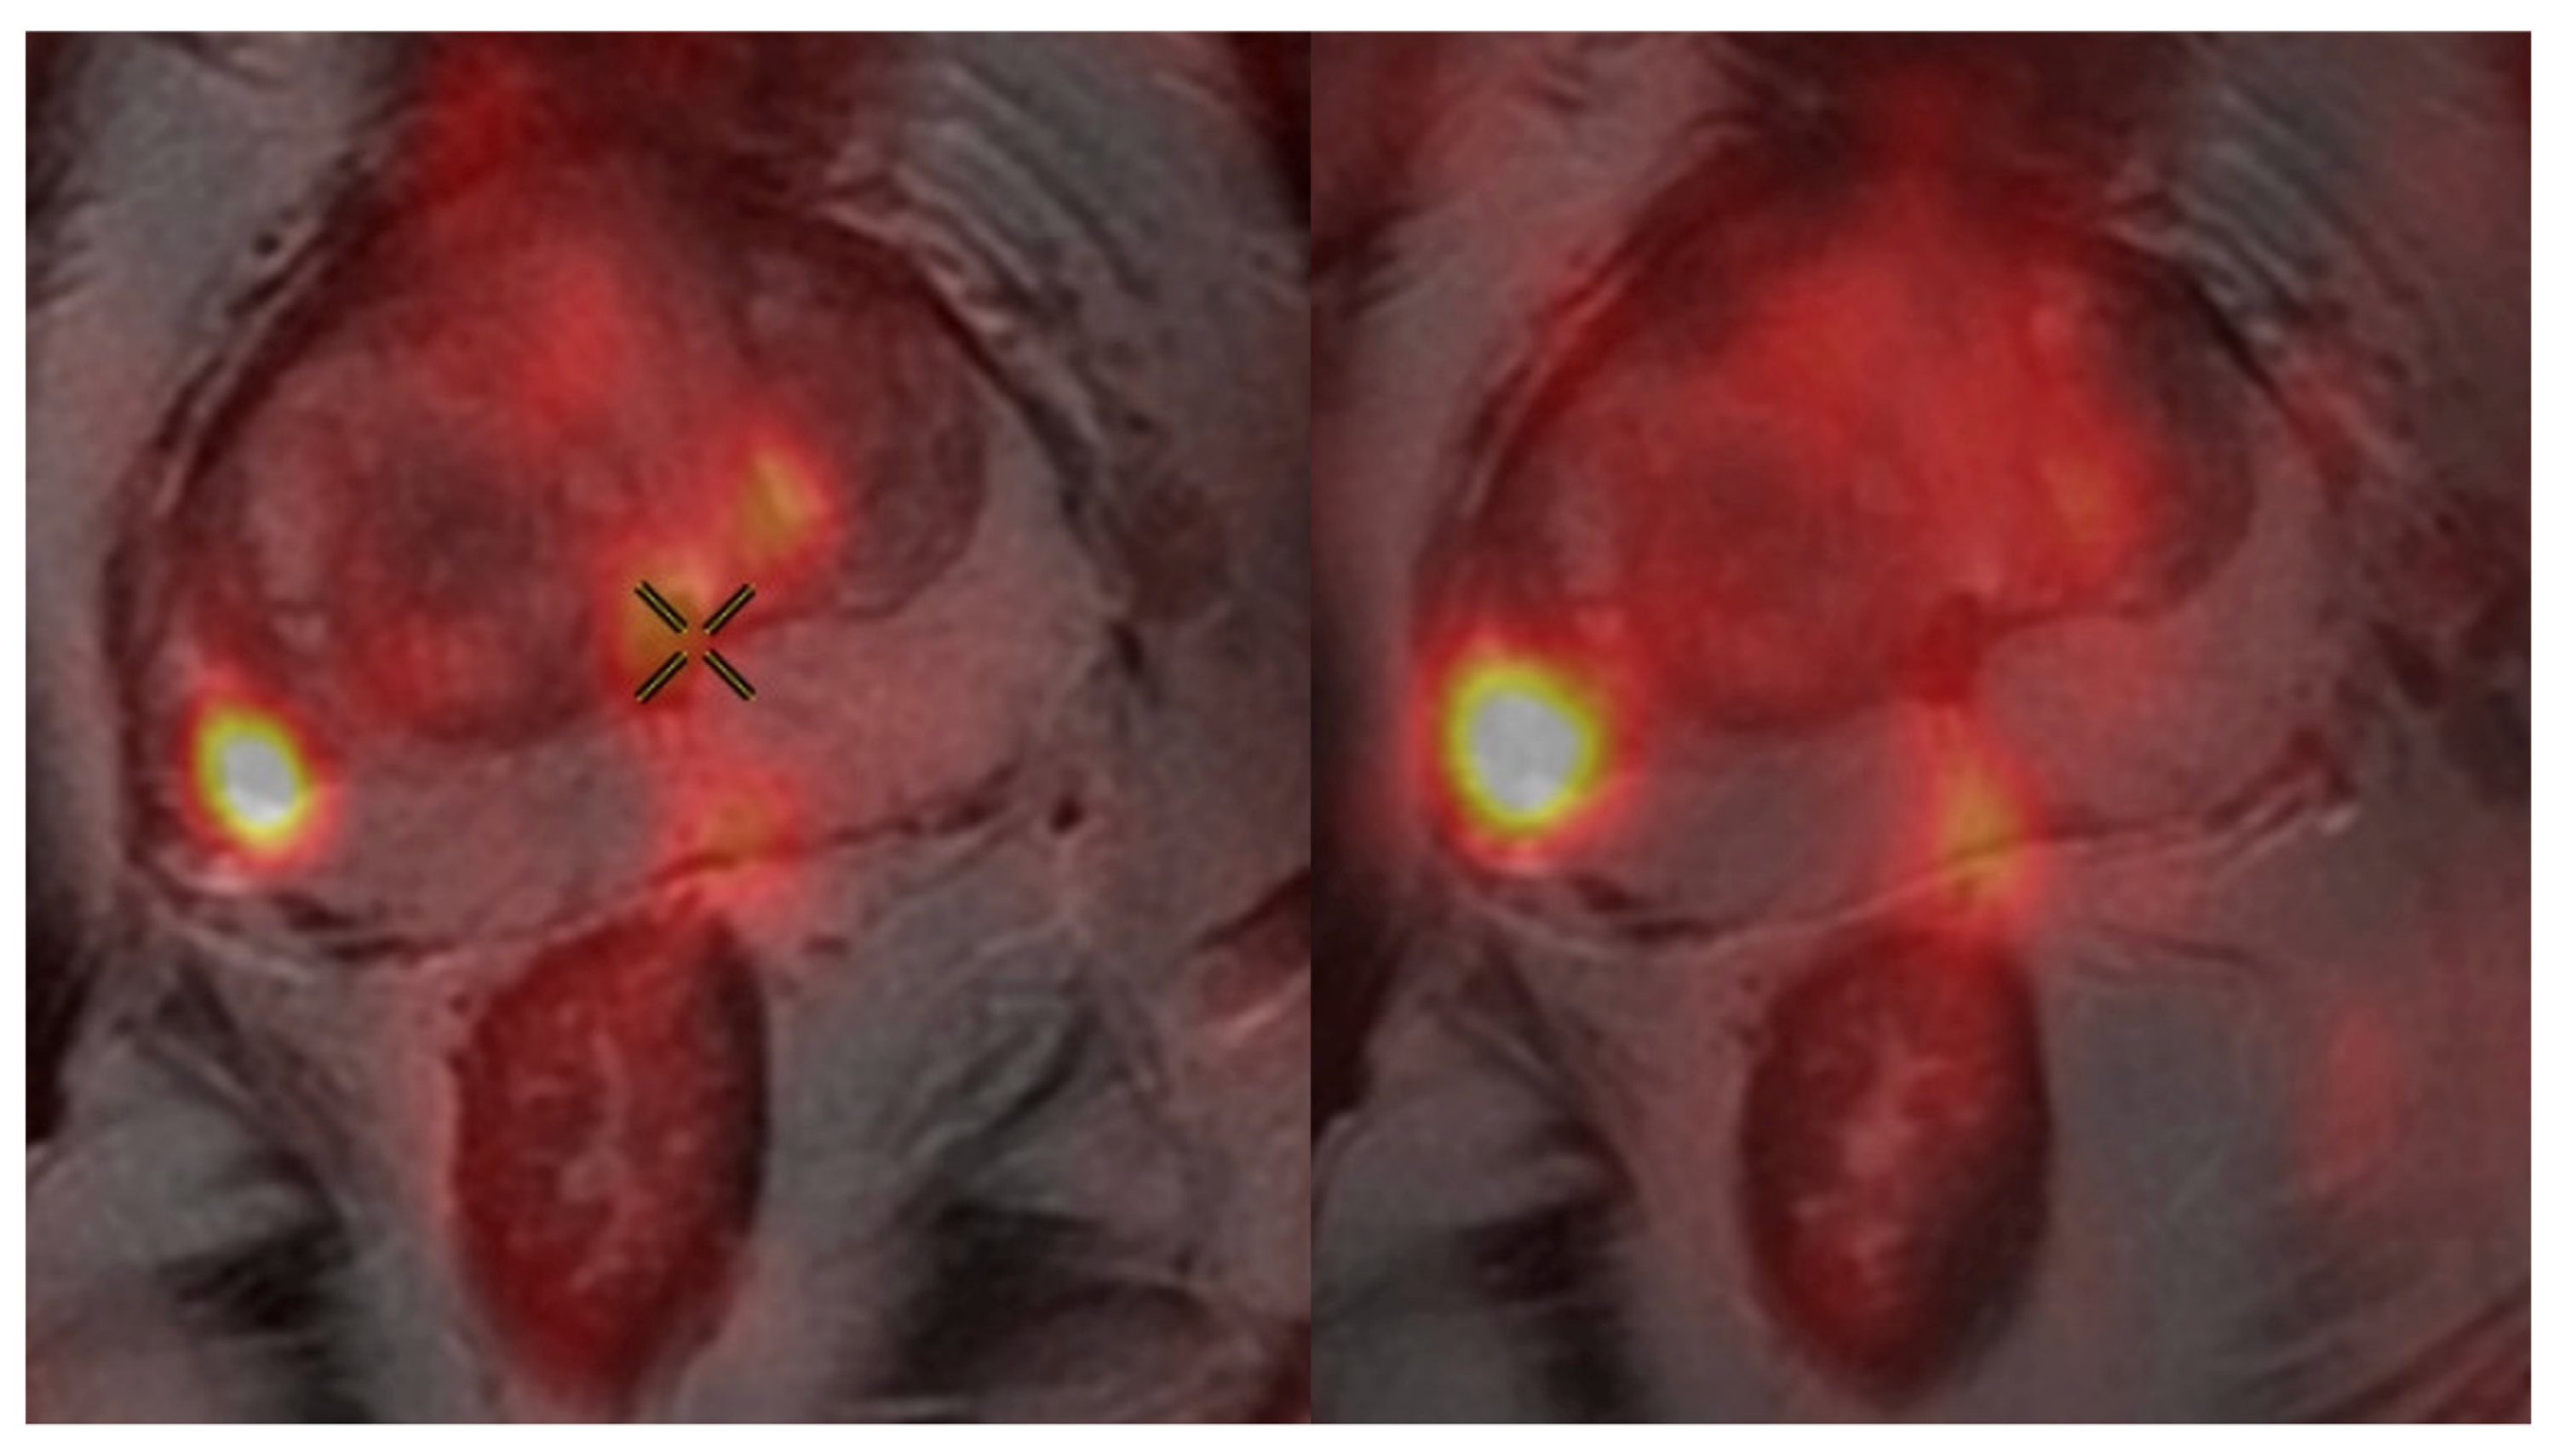

2.3. PSMA PET/CT Protocol

3.2. Impact of Uptake Period on SUVmax